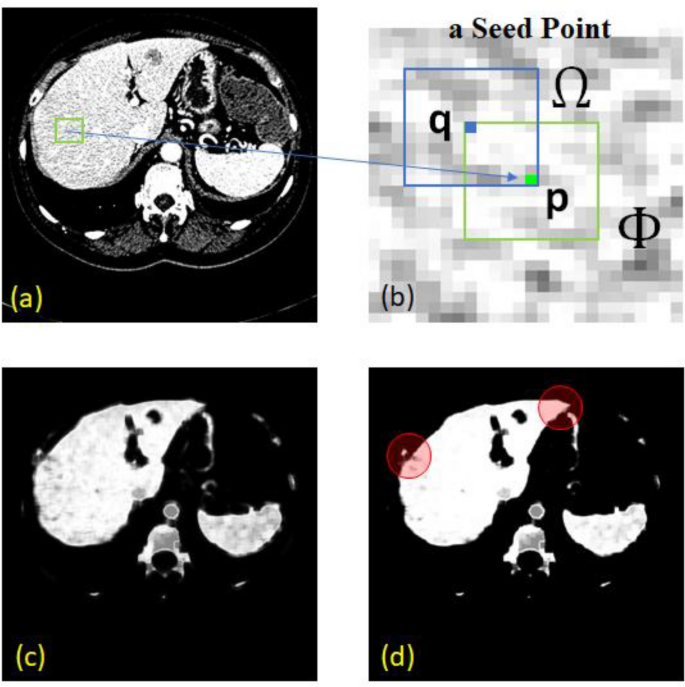

To ensure the performance of the system, the neigbour size was set to only within one pixel proximity in 8 directions. It is also worth noted that, with trivial features, pixel-wise classification may result in vague definitions along connective tissues. To sufficiently enhance such separation prior to the next stage, probabilistic convergence and hence finalized labeling, was not yet required here. The RL was therefore allowed to update, not until convergence, but only for a few iterations. Figure 3 depicts an example configuration of pixel p and its neighbour q, the initial probabilistic map, and the resultant RL enhancement. It is clear that fallacies along the boundary were effectively reduced (red circles).

An example of applying probability map and relaxation labeling. The original CT image (a) with a seed point (green) is shown in (b), the probability map image and RL enhanced results are shown in (c) and (d), respectively. The probability values from 0 to 1 are scaled to 0 to 255 for visualization purpose.